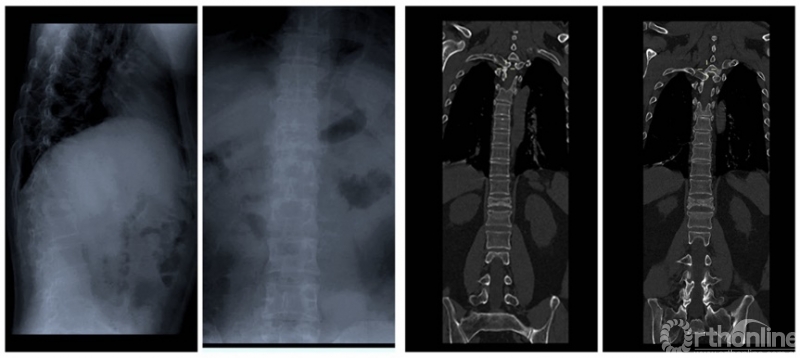

CT提示:肺部磨玻璃样改变;胸12、腰1骨折。核磁共振提示:胸12、腰1压缩性骨折。咽拭子核酸检测阳性。

术前影像学检查

在病情分析会上,会诊医生团队发现患者新冠肺炎的症状并不严重,没有发热,只有咳嗽,且肺部磨玻璃改变范围较为局限,但他的胸腰椎骨折压缩很严重,核磁共振显示椎管侵占已经超过50%,而且有明确的脊髓损伤不全瘫的表现,双下肢肌力均不到2级,感觉严重减退,大小便均失去控制,需要进行抢救性手术治疗。